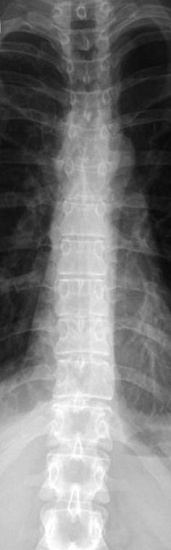

Рентгенография грудного отдела позвоночника – важный метод скринингового исследования, который позволяет оценить состояние грудного отдела позвоночника. Диагностическая услуга выполняется в двух проекциях.

18.3 Рентгенография (цифровая) грудного отдела позвоночника ( 2 проекции, запись на диск) 3 100 ₽